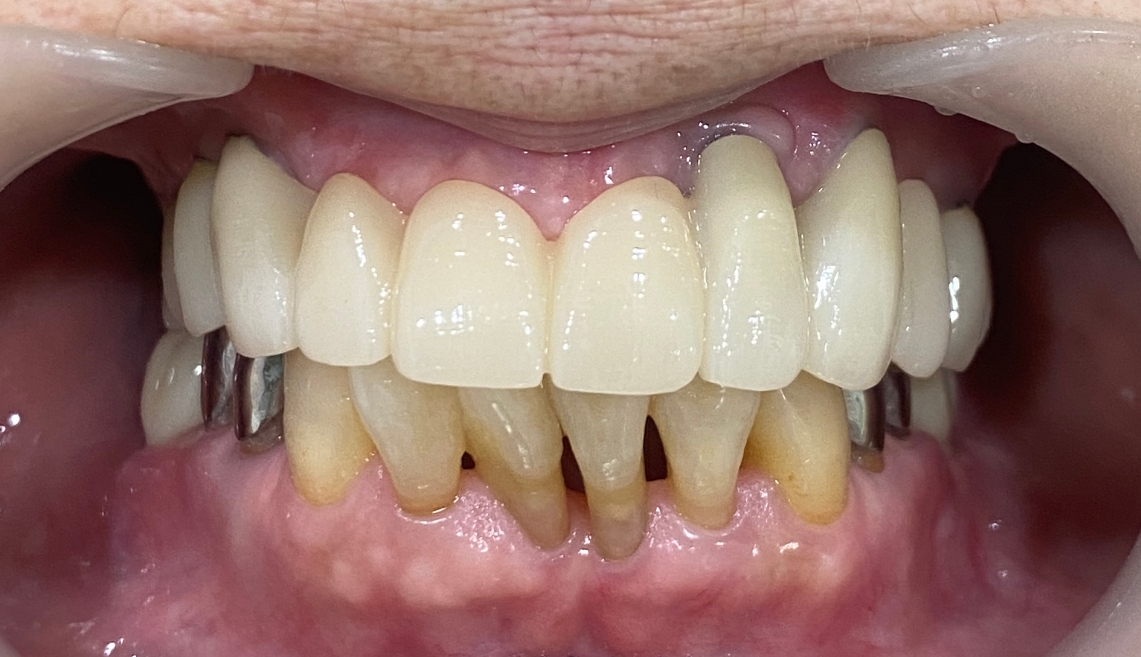

최종 완성후 마지막 교합조정을 하였습니다. 환자분이 잘 사용하고 계셔서 기분이 좋았습니다.